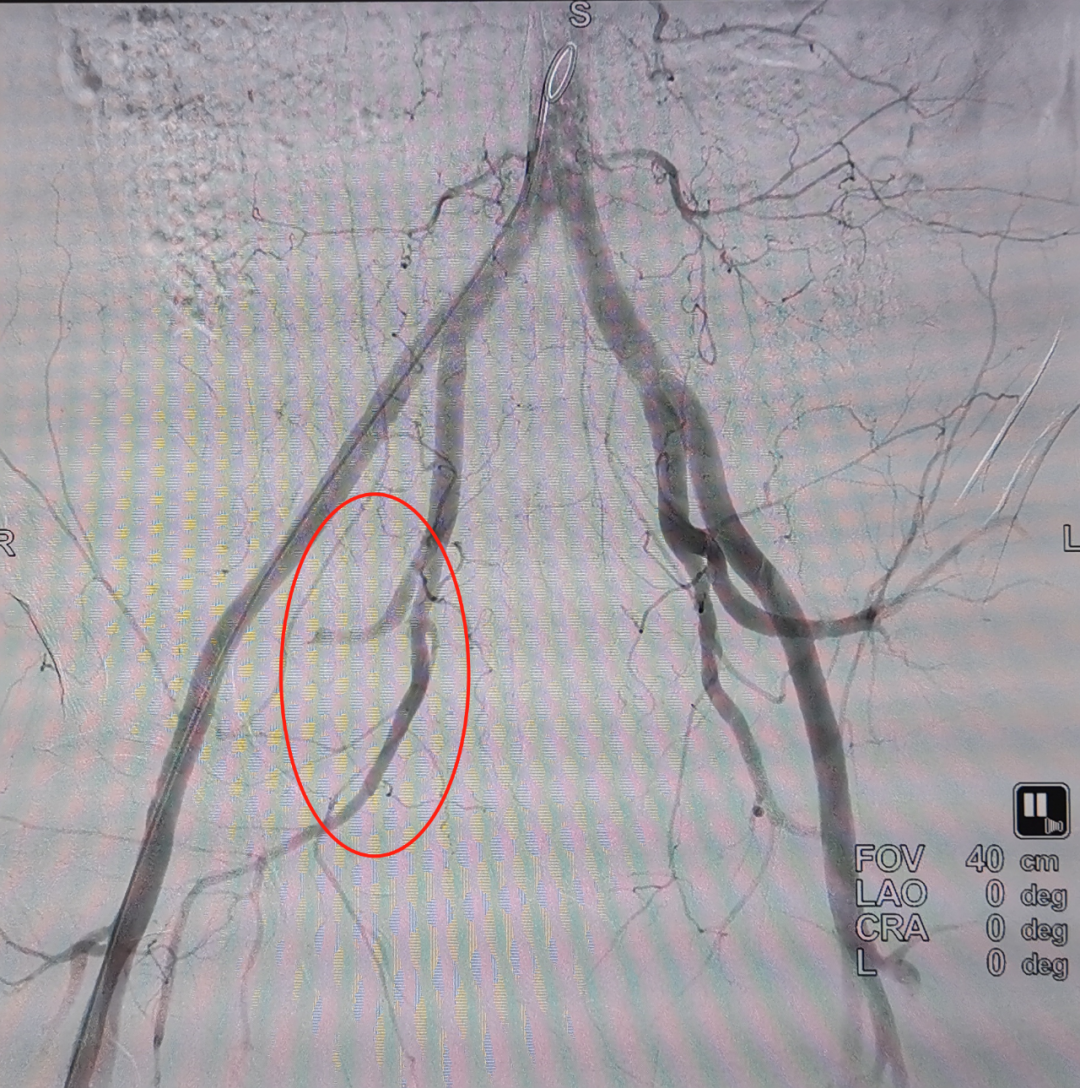

快速分析各項(xiàng)檢查結(jié)果:復(fù)雜的雙側(cè)骨盆開放性粉碎性骨折+髂內(nèi)動(dòng)脈斷裂+尿道斷裂+雙側(cè)多發(fā)肋骨骨折+雙側(cè)血?dú)庑?嚴(yán)重肺挫傷+腹部閉合性損傷+皮下大面積脫套傷+多處血腫等,出血迅猛,病情十分危急。曹飛主任、周春峰主任、介入科孫英豪主任一致認(rèn)為病情非常危急,需立即對(duì)患者進(jìn)行手術(shù),即緊急損傷控制性手術(shù)DCS(介入血管造影+栓塞+骨盆外固定+膀胱造瘺術(shù)),止血、糾正休克及控制傷情進(jìn)一步惡化。

第一次手術(shù)~

第一次栓塞成功~

參與急救的醫(yī)護(hù)人員都長(zhǎng)長(zhǎng)地舒了一口氣,順利完成搶救的第一步。在創(chuàng)傷中心有“黃金1小時(shí)”的理念,即嚴(yán)重創(chuàng)傷患者受傷后1小時(shí)是救治的關(guān)鍵時(shí)期。對(duì)于嚴(yán)重創(chuàng)傷的病人來(lái)說(shuō),時(shí)間就是生命,搶救就是和時(shí)間賽跑,需要爭(zhēng)分奪秒。能否在“黃金期”內(nèi)得到準(zhǔn)確的診斷與治療,往往顯著降低創(chuàng)傷死亡三聯(lián)征的發(fā)生(低體溫、酸中毒、凝血?。瑥亩绊懮媛?。